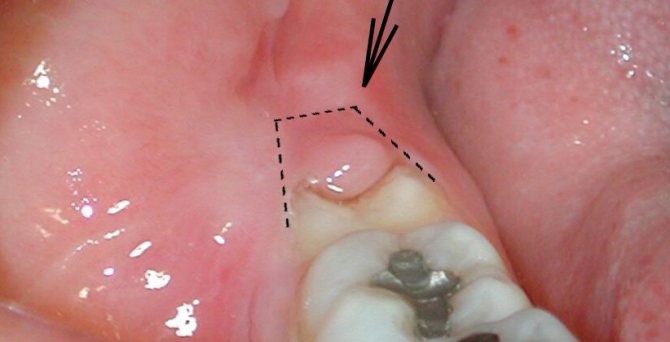

Как выглядят симптомы перикоронита на видео – обратите внимание, что на видео ниже можно увидеть следующие симптомы: покраснение и отек капюшона над верхним зубом мудрости, небольшое количество гнойного отделяемого (белого цвета) из под капюшона. Подобные симптомы соответствуют легкой форме воспаления.

На фото стрелкой указан воспаленный капюшон на зубе мудрости